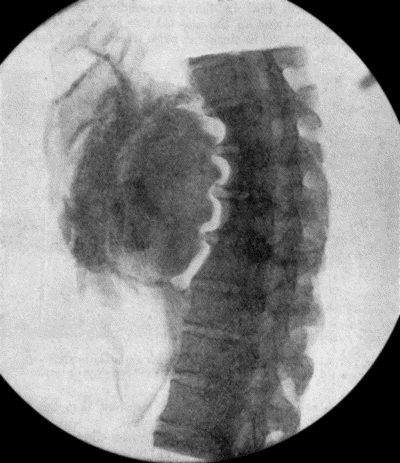

71.Radiogram of Aneurysm of Aorta 303

72.Sacculated Aneurysm of Abdominal Aorta 304